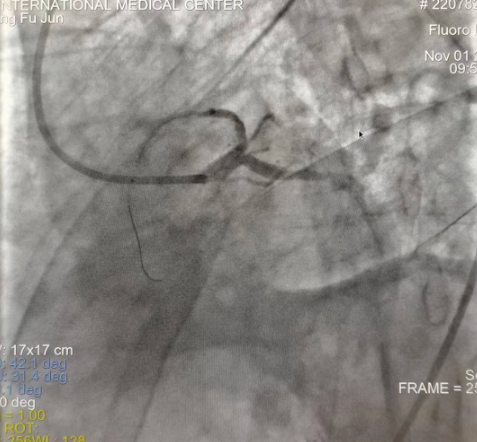

閉塞的血管再通時(shí)間取決于急救時(shí)長、轉(zhuǎn)運(yùn)時(shí)長和治療時(shí)長,在前兩方面,醫(yī)院已為患者爭(zhēng)取了最短時(shí)間。患者家屬遠(yuǎn)在陜北,雖然已在趕來的路上,但最快抵達(dá)西安也要3小時(shí),在與患者家屬電話溝通同意急診手術(shù)后,醫(yī)療總值班代家屬簽字,康曉軍在請(qǐng)示心臟病醫(yī)院王海昌院長及心臟內(nèi)科CCU尚福軍主任后,積極進(jìn)行術(shù)前準(zhǔn)備。在沒有家屬陪同、沒有交費(fèi)、沒有辦入院手續(xù)的情況下,患者經(jīng)胸痛中心綠色通道被送往心臟冠脈介入手術(shù)室,打通了完全閉塞的心臟前降支近段血管。